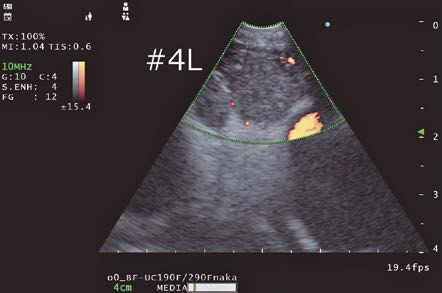

Doppler Modes

Doppler modes are also available with EU-ME3. In my observations, it appears that the Doppler image generated with EU-ME3 exhibited improved resolution compared to EU-ME2. The color blurring was reduced, and the image appeared crisper and clearer. When performing EBUS-TBNA in my facility, we typically use the H-Flow mode which displays blood flow with minimal protrusion from blood vessels to confirm vascular intervention with H-Flow mode before puncturing a lymph node.

Color Flow: Displays direction and velocity of blood flow in color

Power Flow: Displays blood flow intensity in color

H-Flow: Displays direction and intensity of blood flow in color

Pulsed Wave Doppler (PWD): Displays blood flow velocity at a specified location in graph

In this case, blood flow was observed in the upper right of the lymph node where the needle would pass through, so it was necessary to avoid this area when puncturing the lymph node.